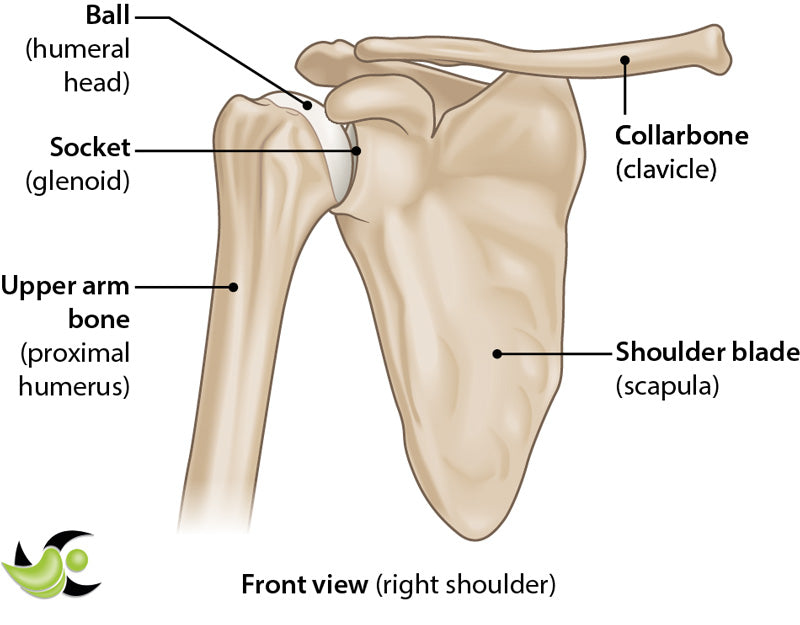

Articular cartilage covers the surface of a bone where it meets with another bone at a joint. In the shoulder, there is articular cartilage covering the head of the humerus (arm bone) and the glenoid (socket bone) where they come together to form the glenohumeral joint. There is also articular cartilage at the ends of the acromion and the clavicle where they meet to form the AC joint. This cartilage is important to provide both a smooth, lubricated surface for joint articulation and to help distribute load to reduce stress on your bones.

Shoulder arthritis occurs when the articular cartilage breaks down and no longer provides a smooth, cushioned surface for bones to glide. This happens naturally due to “wear and tear” associated with aging. You are at higher risk for developing arthritis if it runs in your immediate family, if you have had previous shoulder surgeries, have had a previous shoulder fracture, or if your job occupation/hobbies cause significant stress to your shoulders over many years.